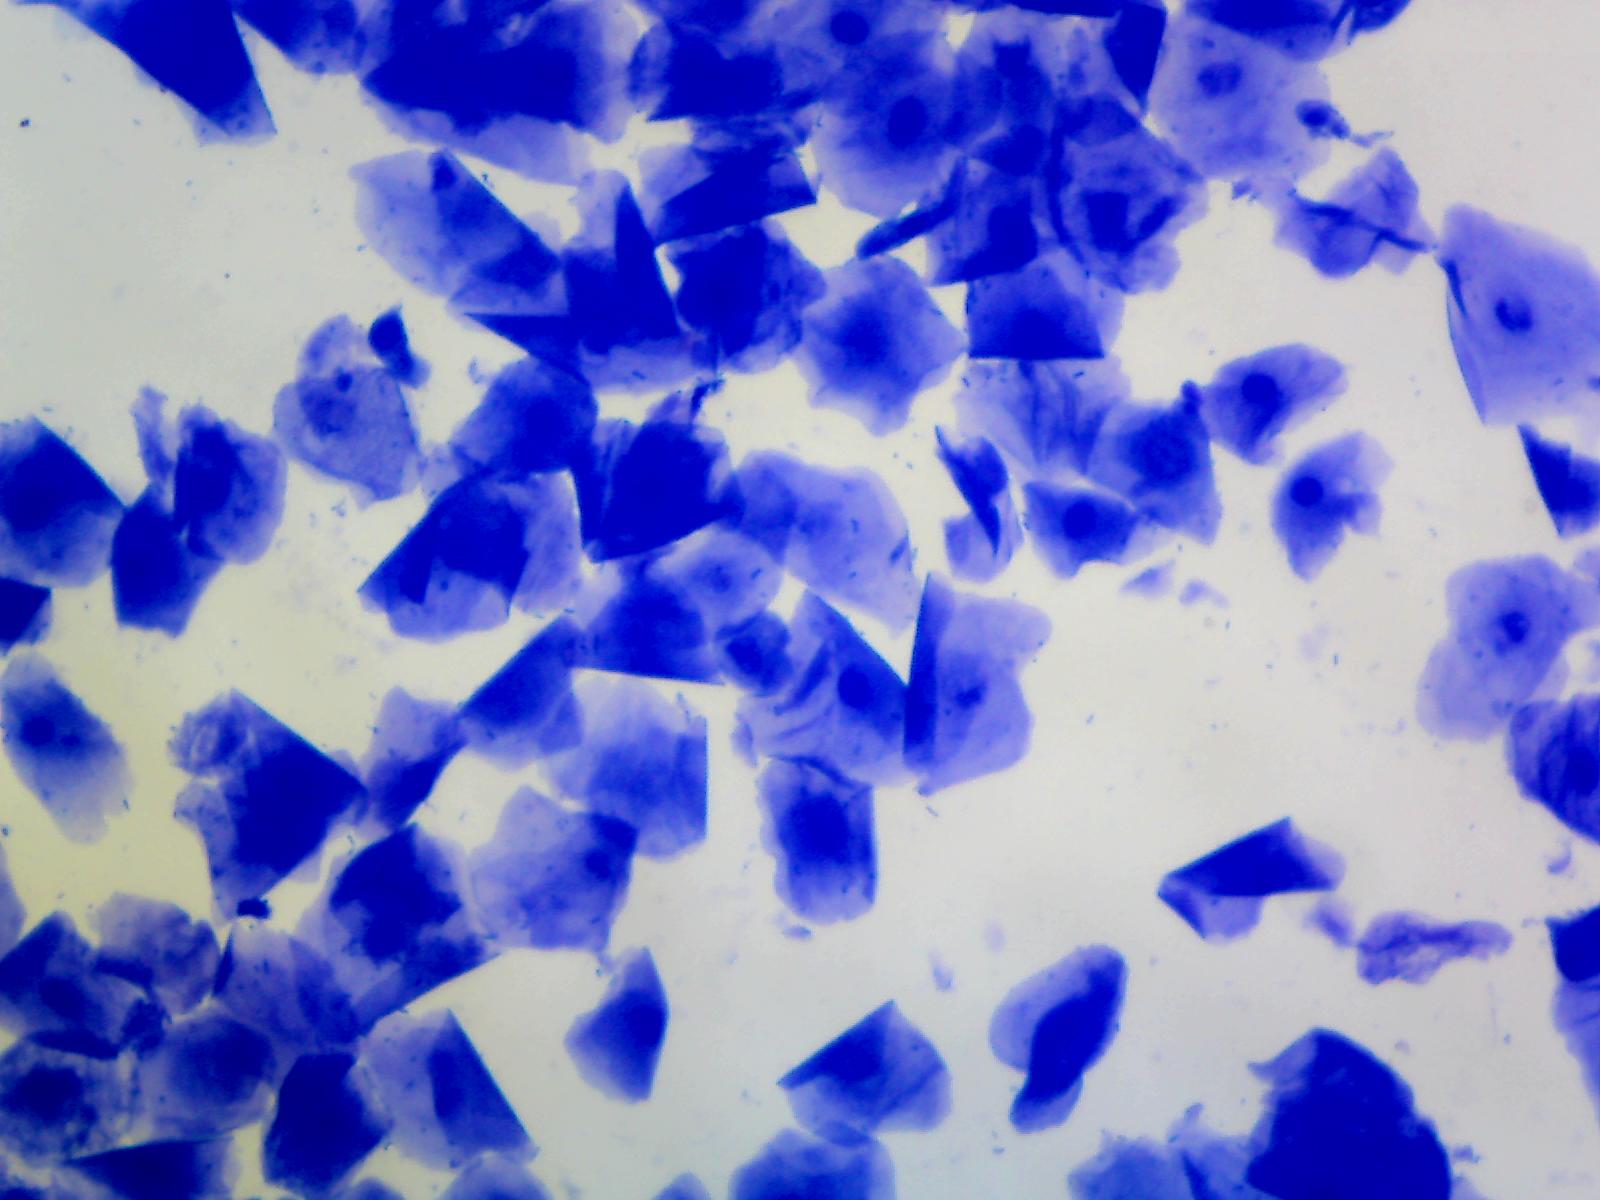

WelcОбратитесь в Calavey Pet Services, где мы стремимся построить отношения с вами и вашими домашними животными на всю жизнь. Мы здесь, чтобы помочь ответственным заводчикам и владельцам собак. Наши услуги варьируются от тестирования на овуляцию до спаривания, беременности и, при необходимости, щенков и выращивания потомства. Я обучен, застрахован и предлагаю только те услуги, которые я компетентен и разрешен законом.